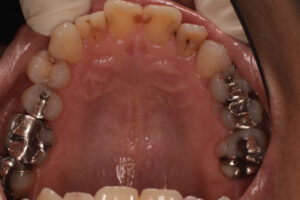

口腔内写真で明らかに違いが判るのは

保険で銀歯→ 自費で白い歯→

レントゲンでは神経の詰め物の状態の違い→